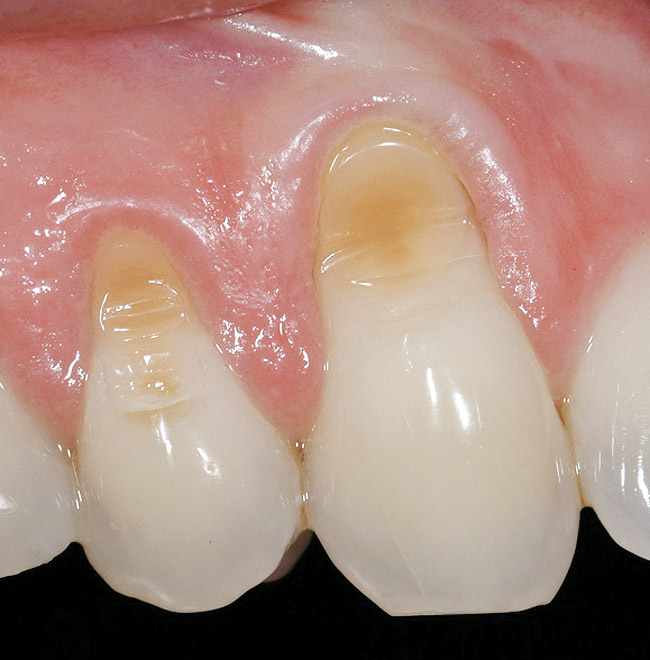

Figure 3  Case One Pretreatment clinical view, Case 1, maxillary left.

Figure 3

A 54-year-old non-smoking woman presented for correction of deep-wide gingival recession in the maxillary anterior (Figure 1 through Figure 3). The patient’s desires were to correct the gingival recession, balance the heights of contour of the tissues, and possibly undergo esthetic enhancement of the maxillary anterior with veneer restorations.

The 2.5-week postoperative clinical view can be seen in Figure 10 through Figure 12. Note the rapid soft tissue healing and maturation. At 6-weeks postoperative, tissue plasty was accomplished to blend the thickened keratinized tissue, in addition to placement of class V composite restorations at teeth Nos. 5, 6, and 11 to create a new restorative margin on the root surfaces.

The 2-month postoperative view can be seen in Figure 13 through 15. Note the color match of the tissue, balance of the facial heights of contour, and zones of attached keratinized tissue present.